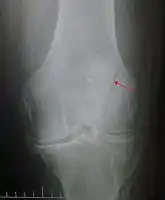

| Patella fracture | |

| A fracture of the patella seen on a lateral view | |

| Diagnostic method | Based on symptom, confirmed with X-rays.[3] |

It typically results from a hard blow to the front of the knee or falling on the knee.[1]The patella can also be fractured indirectly. For example, a sudden contraction of the quadriceps muscle in the knee can pull apart the patella.[1]Diagnosis is based on symptoms and confirmed with X-rays.[3] In children an MRI may be required.[3]

Diagnosis is based on symptoms and confirmed with X-rays.[3] In children an MRI may be required.[3]